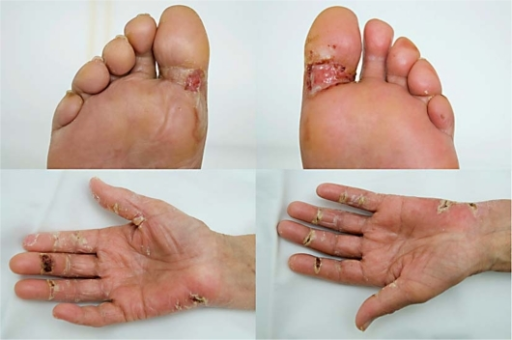

Palmar-Plantar Erythrodysesthesia (PPE) is a dermatologic toxicity associated with a number of chemotherapeutic drugs and some kinase inhibitors. Also known as Hand-Foot Syndrome (HFS), it is characterised by tingling and tenderness developing to symmetrical redness, swelling, and pain primarily on the palm of the hand and sole of the foot.

Palmar-plantar erythrodysesthesia associated with chemotherapy and its treatment by K. P. Farr and A. Safwat is licensed under CC BY-NC-ND 3.0.